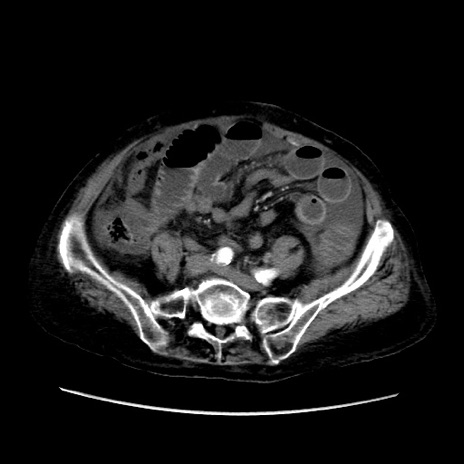

矢状断像

【症例】80歳代 女性

【主訴】腹部膨満感

【現病歴】他院にて肝硬変にてフォロー中。1週間前から便秘、腹部膨満感、臍部腫瘤あり受診となる。

【既往歴】肝硬変

【身体所見】腹部膨隆あり、皮膚変化なし、疼痛なし。

【データ】WBC 4600、CRP 0.25